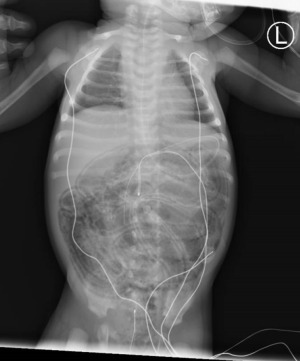

A 2-week-old female infant was admitted to the pediatric emergency department (PED) at Soroka University Medical Center (SUMC) because of a 5-day history of vomiting associated with blood in stool on the day of admission. Her prenatal history was normal, with a full-term baby, a gestational age of 38 weeks, and a standard prenatal follow-up. The delivery was spontaneous vaginal, with a birth weight of 3,030 grams. The immediate perinatal course was reported as uneventful. She was initially fed with cow’s milk-based formula, but did not gain weight. On admission, she appeared weak and apathetic; her blood pressure was 76/56 mmHg, her heart rate was 160 beats/minute, her respiratory rate was 48 per minute, and her body temperature was 36.6 ℃. Her weight was 2,600 grams. Her extremities were cold; capillary refill time was two seconds, and a cutis marmorata skin was present. She had a distended abdomen, with no signs of peritonitis or skin discoloration, and no hepatosplenomegaly; other findings were normal. Lab results showed metabolic acidosis with a wide anion gap (pH 7.33, bicarbonate 12.7, pCO2 24) and high lactate levels (6.0 mg/dL; normal values 0–1.5 mg/dL). The complete blood count results were within the normal range. Her blood chemistry results showed urea at 29mg/dL, sodium at 130 mEq/L, with normal creatinine, albumin at 3.4 mg/dL, and normal liver transaminases. A nasogastric tube was inserted, and fecal content was drained. Abdominal X-ray showed a diffuse PI without any sign of bowel perforation (shown in Figure 1).

In this case, we present a full-term healthy neonate who presented with late-onset diffuse PI with fecal emesis, without any evidence of infection; the patient’s history and social worker weren’t impressed with child abuse, and there were no risk factors for late-onset NEC. The working diagnosis was PI secondary to CMP allergy, which was managed successfully conservatively without any invasive procedure despite the impressive abdominal X-ray findings and her presenting symptoms.